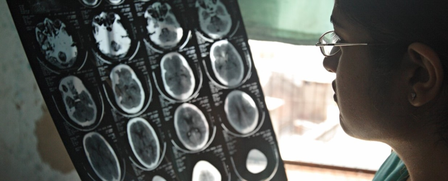

नई दिल्ली, 14 अक्टूबर (आईएएनएस)। विश्व स्वास्थ्य संगठन (डब्ल्यूएचओ) की मंगलवार को जारी एक नई रिपोर्ट के अनुसार, दुनिया भर में हर तीन में से एक व्यक्ति ऐसी स्थितियों के साथ जी रहा है जो उसके मस्तिष्क को प्रभावित करती हैं, जबकि तंत्रिका संबंधी विकारों के कारण हर साल 11 मिलियन (1 करोड़ दस लाख) लोगों की जान चली जाती है।

नई दिल्ली, 14 अक्टूबर (आईएएनएस)। विश्व स्वास्थ्य संगठन (डब्ल्यूएचओ) की मंगलवार को जारी एक नई रिपोर्ट के अनुसार, दुनिया भर में हर तीन में से एक व्यक्ति ऐसी स्थितियों के साथ जी रहा है जो उसके मस्तिष्क को प्रभावित करती हैं, जबकि तंत्रिका संबंधी विकारों के कारण हर साल 11 मिलियन (1.1 करोड़) लोगों की जान चली जाती है।

स्ट्रोक, नवजात शिशु मस्तिष्क विकृति, माइग्रेन, अल्जाइमर रोग और अन्य मनोभ्रंश, डायबिटिक न्यूरोपैथी, मेनिन्जाइटिस, इडियोपैथिक एपिलेप्सी, समय से पहले जन्म से जुड़ी तंत्रिका संबंधी जटिलताएं, ऑटिज्म स्पेक्ट्रम विकार और नर्वस सिस्टम कैंसर को मृत्यु और विकलांगता में योगदान देने वाली शीर्ष 10 तंत्रिका संबंधी स्थितियों के रूप में पहचाना गया।

रिपोर्ट में कहा गया है कि हालांकि ये तंत्रिका संबंधी स्थितियां अब वैश्विक आबादी के 40 प्रतिशत से अधिक को प्रभावित करती हैं, फिर भी दुनिया में तीन में से एक से भी कम देशों के पास न्यूरोलॉजिकल डिसऑर्डर (तंत्रिका संबंधी विकारों) से निपटने के लिए कोई राष्ट्रीय नीति है।